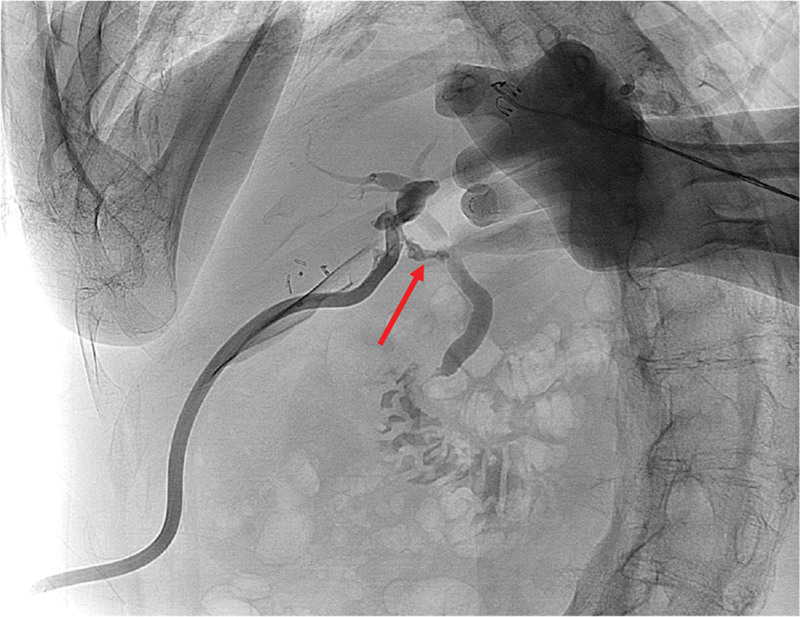

On the fourth day after the surgery, bile leakage was observed through the surgical drain (Fig. 1). As a result of his poliomyelitis, he had a limited degree of mouth opening due to trismus and stiffness in both arms across his chest. He could not receive transoral ERCP or PTBD. Therefore, LA-ERCP was performed.

An additional 15-mm port was inserted in the left upper quadrant and gastrotomy was introduced in the midline of the purse-string suture. The stomach was lifted to the anterior abdominal wall after the purse-string suture was tightened. An endoscope was introduced through the 15-mm port (Fig. 2). ERCP, sphincterotomy, and 7-Fr × 10 cm endoscopic retrograde biliary drainage (ERBD) insertion at the leak site were performed (Fig. 3). After ERBD insertion, a 26-Fr balloon bumper percutaneous endoscopic gastrostomy (PEG) catheter was inserted through the 15-mm trocar site for reintervention and stent removal. The bile leakage healed 2 days after the procedure. The patient was discharged without any complications on the fifth day.